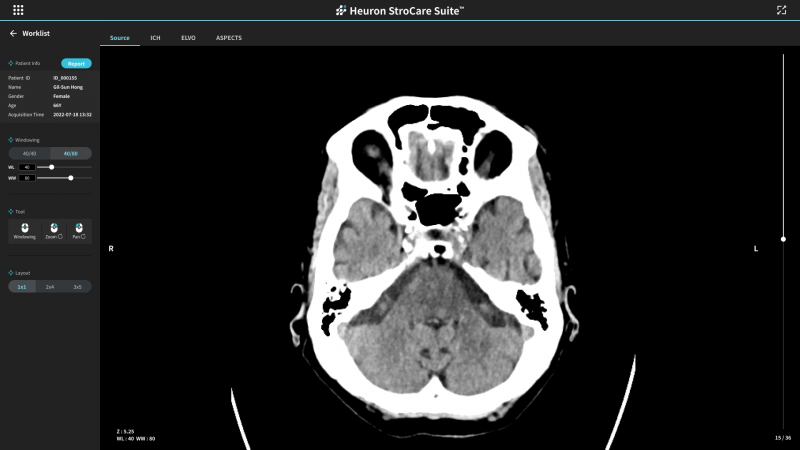

휴런(대표 신동훈)은 비조영 CT 영상을 활용한 인공지능(AI) 기반 응급 뇌졸중 선별 솔루션인 ‘Heuron StroCare Suite’가 보건복지부 혁신의료기기 통합심사 평가 고시를 통해 혁신의료기술로 지정받았다고 15일 밝혔다.

휴런 스트로케어 스위트는 비조영 CT만으로 응급 뇌 대혈관 폐색 여부를 분석하는 AI 솔루션이다. 응급실에 내원한 급성 뇌졸중환자 뇌 CT 영상을 자동 분석해 대혈관폐색 의심 환자를 선별하고 우선 판독을 위한 의료진 알람 서비스를 제공한다.

응급 뇌 대혈관 폐색 환자 우선 순위 분류를 통해 치료 개시 시간을 단축시켜 골든타임 내 환자를 빠르게 치료하는 데 도움이 돼 뇌졸중 환자 예후 개선을 기대할 수 있다.